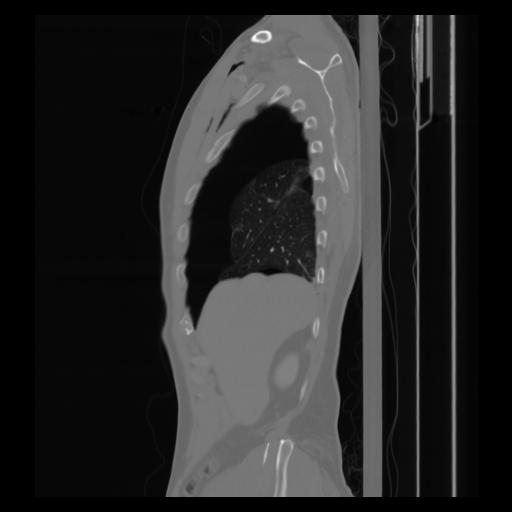

30 CUERPO,CE,Sagittal,3.000,CUERPO,Sagittal,